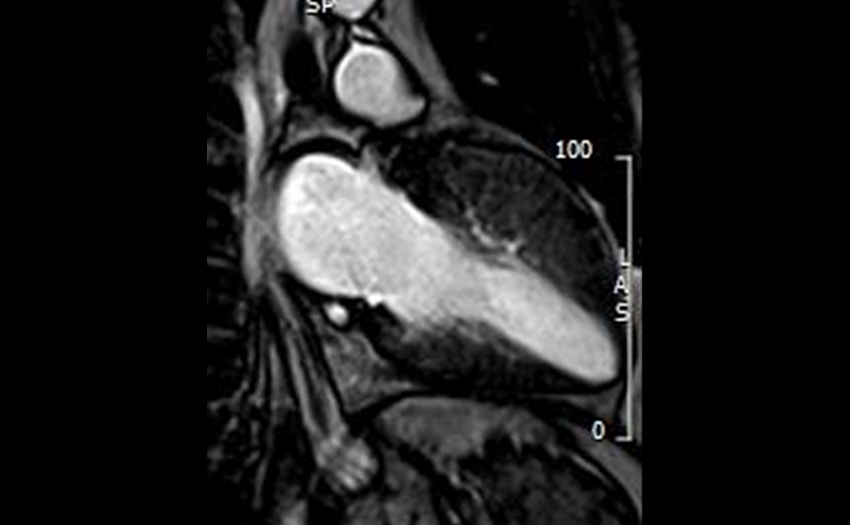

- Cardiac MRI: Additional training possible in Cardiac MRI in collaboration with both the Cardiology and Radiology departments.